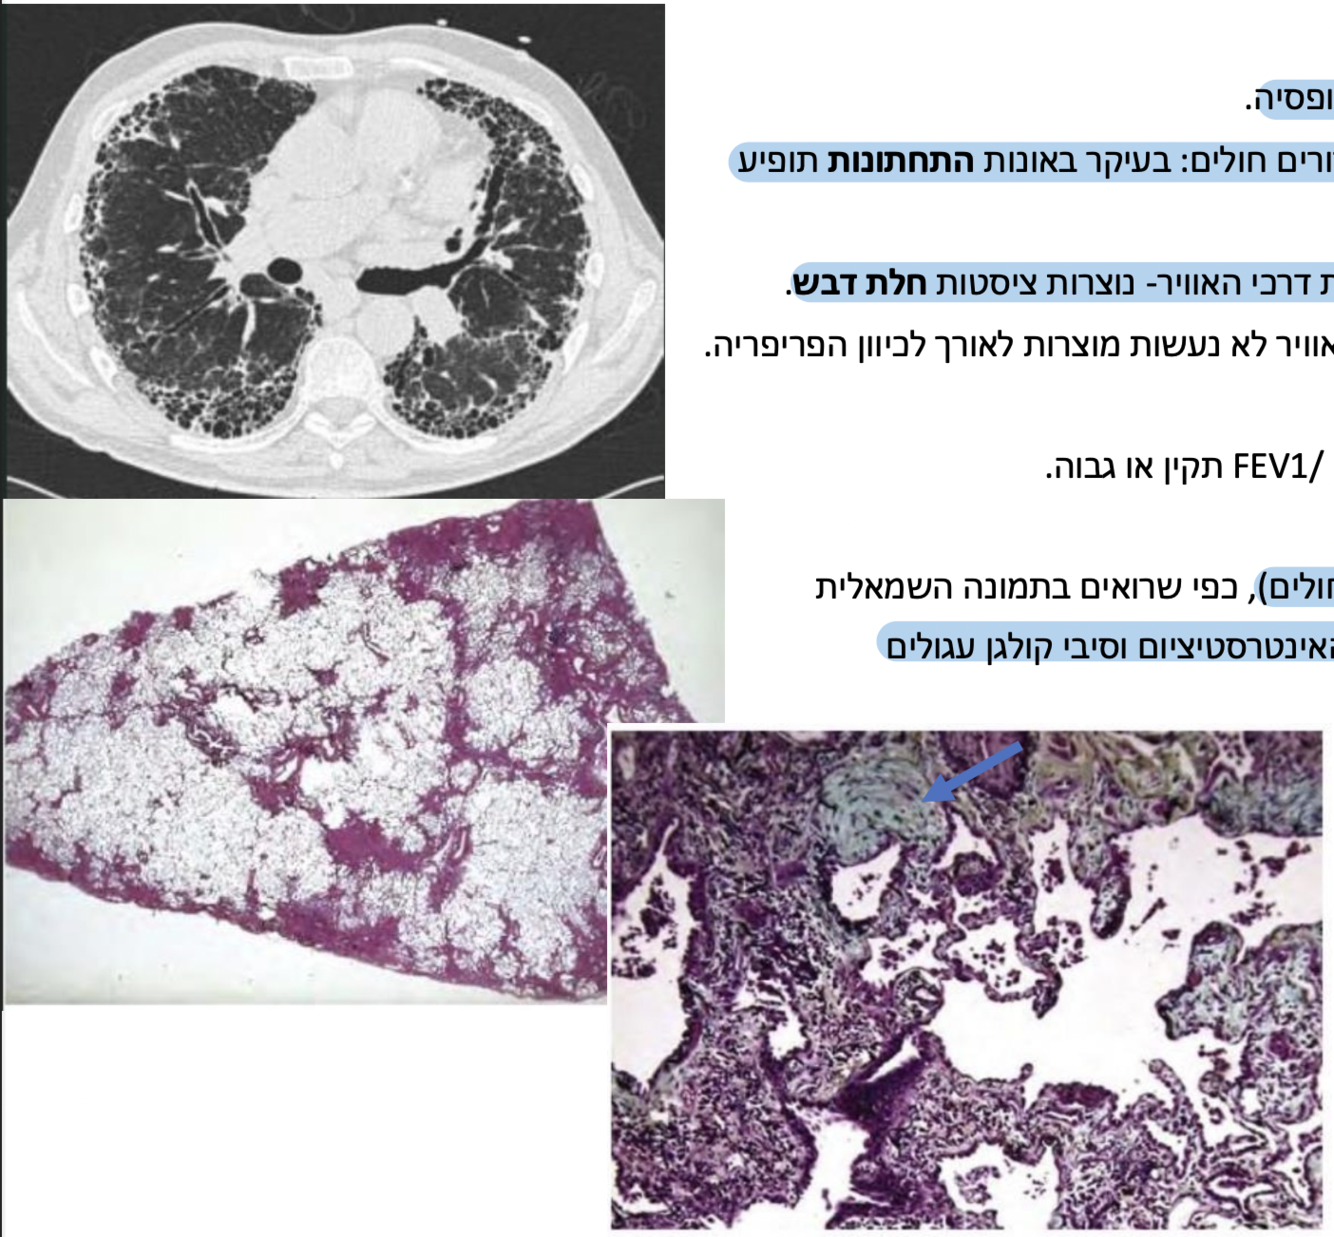

)non specific interstitial Pneumonia( NSIP מה המאפיינים של?

קשור בדכ למחלה סיסטמית אחרת- מחלות רקמת חיבור,

תגובה לתרופה, IBD

דלקת ריאות היפרסנסיטיבית- תגובת גיוס לימפוציטים עקב חשיפה לחומר אורגני, תגובה דלקתית ולא חיידקית.

בצעירים, נשים, לא מעשנים.

Ground glass בסיטי יהיה מראה של

טיפול- אימונוסופרסיבי במינון גבוה ממושך, עוצר את פעולות מערכת החיסון.